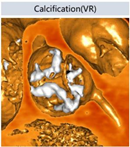

该病例为三叶瓣,瓣叶钙化较重且分布均匀,瓣膜移位风险较低。按照瓣环尺寸及瓣上狭窄情况,应选择植入TAV27型号瓣膜。然而右窦方向窦宽较窄,右冠瓣钙化较左、无较轻,虽然冠脉开口高度尚可,但瓣叶冗长,瓣膜植入后有影响右冠血流的可能。因此,为减少对右冠供血的影响,综合考虑起搏器植入的可能性,植入深度选择稍深,目标植入深度选择5-6mm较为合适。